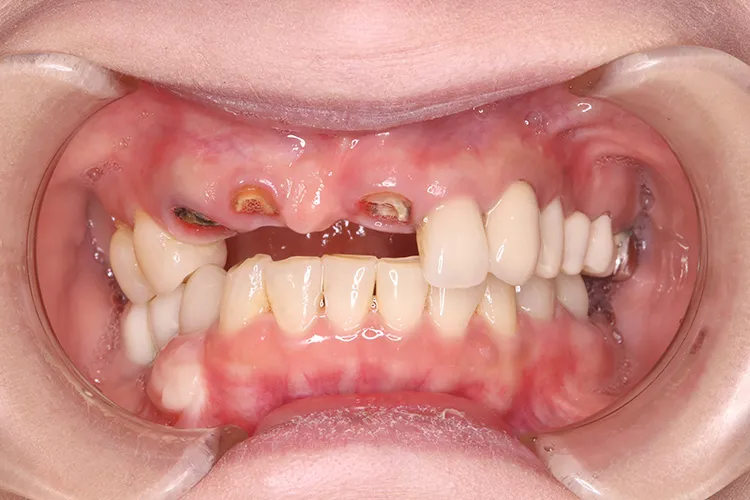

治療内容

左下67 欠損に対してインプラント治療を行った症例

部分床義歯を使用していたが、どうしても慣れない上にしっかり噛むことができないためインプラント治療を希望